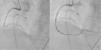

Foi orientada para angioplastia primária, não sendo passível a sua execução por via radial pela tortuosidade da artéria subclávia (Figura 1A). O acesso femoral foi dificultado pela ausência de pulso, sendo a punção guiada por contraste (Figura 1B e 1C); constatou‐se oclusão da ilíaca externa, ultrapassada utilizando uma guia hidrofílica. Observou‐se oclusão do segmento médio da coronária direita por trombo (Figura 2A), sendo realizada trombectomia (Figura 2B).

Cateterismo esquerdo: (A) cateterização por via radial impossibilitada pela tortuosidade da artéria subclávia, que impedia a progressão do fio‐guia; (B) punção da artéria femoral esquerda guiada por contraste; (C) durante a cateterização por via femoral, era aparente uma estrutura (seta) filiforme e móvel, sugestiva de trombo.